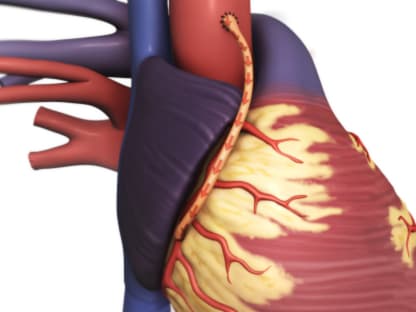

Atherosclerosis occurs when fatty deposits called plaque build up inside arteries. Arteries are the blood vessels that carry oxygen-rich blood throughout your body. When plaque builds up in the arteries that supply blood to the heart muscle (the coronary arteries), it is called coronary artery disease. Over time, the plaque may narrow the arteries and reduce blood flow to the heart muscle.

Coronary artery disease most often begins when the inside walls of the coronary arteries are damaged because of another health problem, such as high cholesterol, high blood pressure, diabetes, or smoking. This damage can lead to atherosclerosis, or hardening of the arteries. This means that plaque, made of fats and other substances, builds up in the coronary arteries.

Atherosclerosis can get worse over time. As plaque builds up in the arteries, they may become narrow. This can reduce blood flow to the heart muscle. This is called ischemia (say "is-KEE-mee-uh"). Ischemia can cause angina symptoms, such as chest pain or pressure.